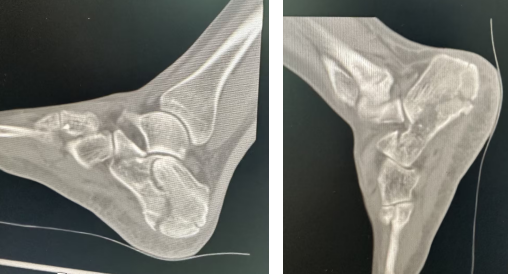

(术前)

(术后)